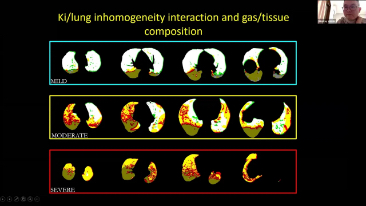

Wyb├│r odpowiedniego ustawienia respiratora do leczenia pacjent├│w z chorob? dr├│g oddechowych to bardzo wa?na kwestia. Poniewa? zadanie polegaj?ce na okre?leniu parametr├│w sprz?tu do wentylacji jest wykonywane w ca?o?ci przez lekarza, wiedza i do?wiadczenie lekarzy w wyborze tych parametr├│w ma bezpo?redni wp?yw na dok?adno?? podejmowanych decyzji. Paradygmat opieki ze wsparciem dla pacjent├│w zmieni? si? znacz?co w ci?gu ostatnich 20 lat. Na podstawie analiz potrzeb klinicznych opracowano r├│?ne tryby wentylacji i narz?dzia wspomagaj?ce podejmowanie decyzji, aby pom├│c opiekunom zwi?kszy? efektywno?? i zminimalizowa? ryzyko b??d├│w w podejmowaniu decyzji klinicznych.

??cz?c w jednym urz?dzeniu wysokoprzep?ywow? terapi? tlenow?, wentylacj? nieinwazyjn? i wentylacj? inwazyjn?, respiratory typu 3 w 1 z serii SV zapewniaj? stabilne dzia?anie, wszechstronne funkcje i ?atwo?? u?ytkowania. Unikalne funkcje ochrony p?uc i wiele narz?dzi wspomagaj?cych podejmowanie decyzji zosta?y opracowane w celu zmniejszenia ryzyka zaka?eń krzy?owych i u?atwienia opiekunom wykonywania codziennych obowi?zków.